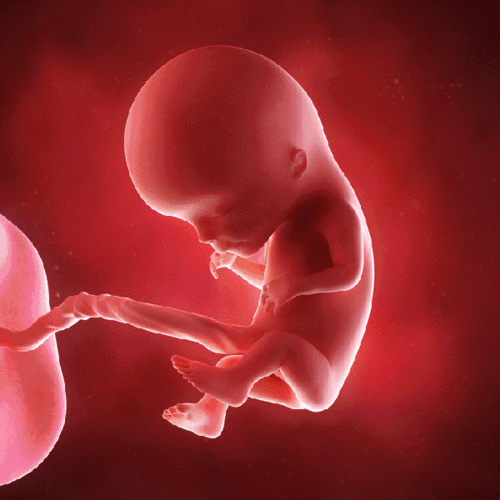

怀孕5-9周"胚胎"分化成"胎儿",生命就是这么神奇!附注意点

进入4个月,胎儿的小耳朵从这个月起可以听到子宫外的声音了.

进入4个月,我的小耳朵从这个月起可以听到子宫外的声音了,呵呵.